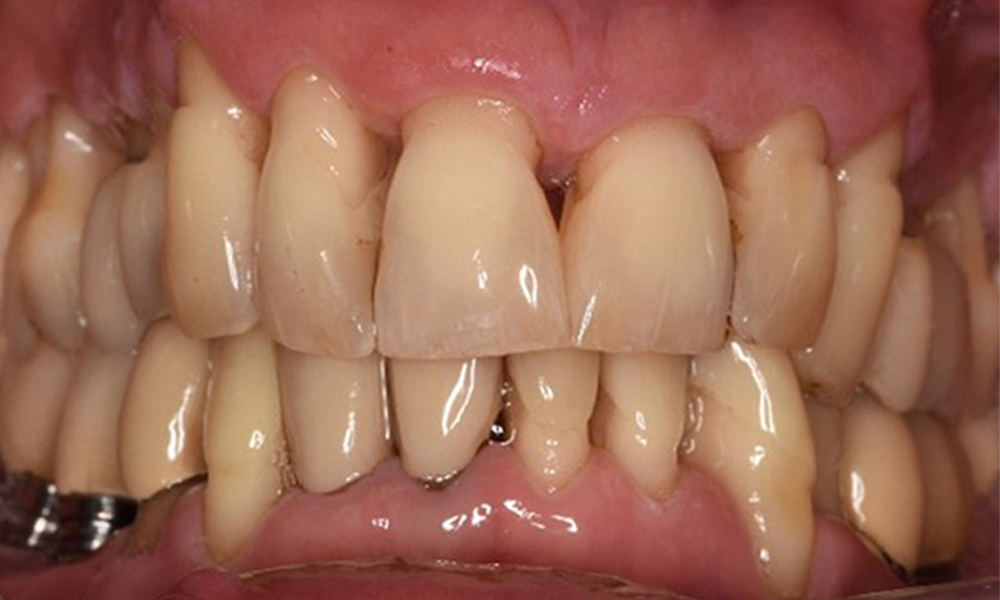

Ein 52-jähriger Patient stellt sich zur Präventionssitzung vor. Der Patient hat keine Allgemeinerkrankungen und nimmt keine Medikamente ein. Er hat verschiedene zahnärztliche Versorgungen und zudem zwei aktive kariöse Läsionen. Außerdem verfügt der Patient über vier Implantate (2., 3. und 4. Quadrant). Es zeigt sich eine parodontale Vorerkrankung (Stadium IV, Grad B). Derzeit herrschen stabile parodontale Verhältnisse, lediglich am Implantat regio 36 zeigen sich Sondierungstiefen (ST) von 5 mm. Zudem lässt sich eine Gingivitis feststellen.

Die Mundhygiene und Mitarbeit des Patienten sind sehr gut (siehe Abbildung "Frontansicht"). Es bedarf lediglich der Reinstruktion und Motivation zum Aufrechterhalten des Mundhygieneverhaltens.